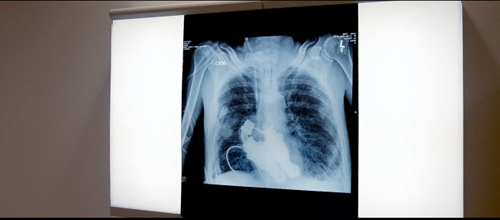

被植入病人体内的离心泵被植入病人体内的离心泵 两位美国医生证明了没有心脏人照样可以存活两位美国医生证明了没有心脏人照样可以存活 接受手术的患者接受手术的患者

新浪科技讯 北京时间2月7日消息,两位美国医生:比利·科恩(Billy Cohn)和巴德·弗朗茨(Bud Frazier)都来自美国德克萨斯心脏研究所,日前他们两人成功地为一名垂死的患者安装了一台人工装置以替代其心脏功能。这一举动证明了,即便没有心脏,一个人也能依靠其他替代手段存活。

在Focus Forward 影片公司制作的短片《当心脏停止跳动》当中,导演杰里米·撒加(Jeremiah Zagar)纪录下了医生们手术操作的全过程——他们在50头小牛身上进行了实验,将它们的整个心脏取出,并用一台特制的离心泵取而代之;最后医生们在一位病人——克莱格·莱维斯(Craig Lewis)身上进行了实际操作。这个离心泵装置有点像是一台涡扇,装有简单的转子结构。这台装置并不会像心脏那样跳动,其目标是像花园里的浇水管一样提供“连续不断的血流”。

在对一头小牛进行实验之后,科恩说:“如果你用听诊器听听它的胸腔,你不会听到心跳声。如果你观察它的动脉,你也观察不到脉搏。如果你对它进行心电图检查,你会看到一条直线。”

病人克莱格·莱维斯今年55岁,由于患有淀粉样变性而生命垂危,这种病会导致异常蛋白质不断累积。这些蛋白质会阻塞器官组织,造成它们无法正常工作。但在手术之后,病人的心脏被“机器”替代。莱维斯的血液继续在他的体内循环流动。

然而当医生们用听诊器听他的胸腔时,却听不到心跳声,有的只是轻微的嗡嗡声而已。因此,如果按照传统的医学分析方法,这位病人已经没有心跳,因而已经死亡了。这是一个例证,证明“人体的生理系统是可以没有脉搏而维持正常运行的。”(晨风)